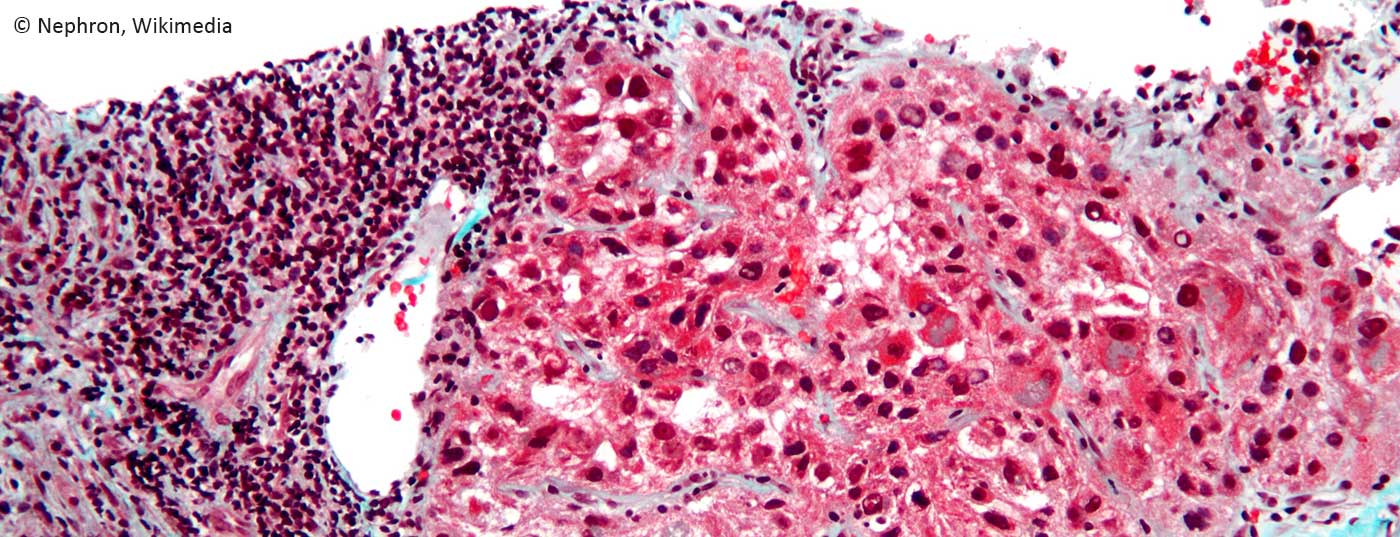

hepatocellular_carcinoma_intermed_mag

• Hepatozelluläres Karzinom

Moderne Therapieoptionen

Kurative Therapien beim hepatozellulären Karzinom sind chirurgische Resektion, Ablation und Lebertransplantation. An der Zürcher Konsensus-Konferenz 2010 wurden international gültige Empfehlungen für Lebertransplantationen bei HCC formuliert.